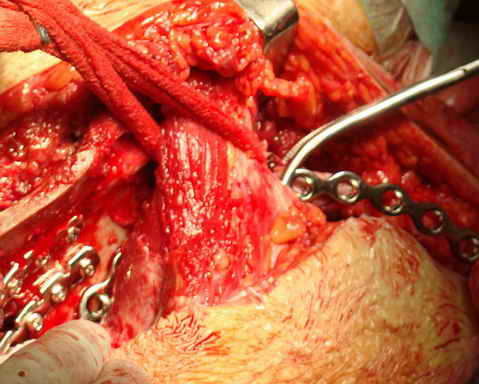

Перелом. Внутритазовый обзор.

Остеосинтез подвздошной кости

Операционная. Оперирует д.м.н. проф. Казанцев А.Б.